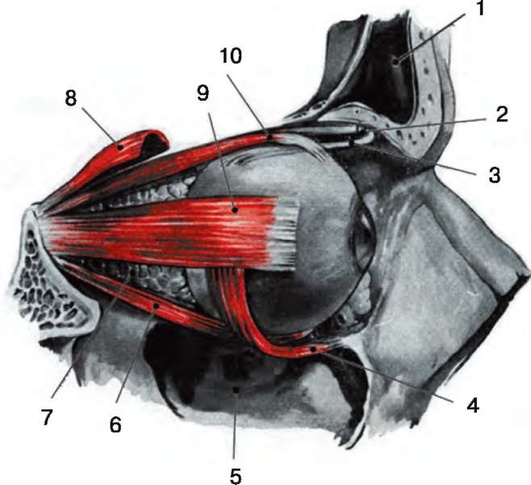

Рис. 3.2. Наружные мышцы глаза: 1 - лобный синус; 2 - блоковый выступ; 3 - сухожилие верхней косой мышцы; 4 - нижняя косая мышца; 5 - верхнечелюстной синус; 6 - нижняя прямая мышца; 7 - жировое тельце орбиты; 8 - мышца, поднимающая верхнее веко; 9 - латеральная прямая мышца; 10 - верхняя прямая мышца